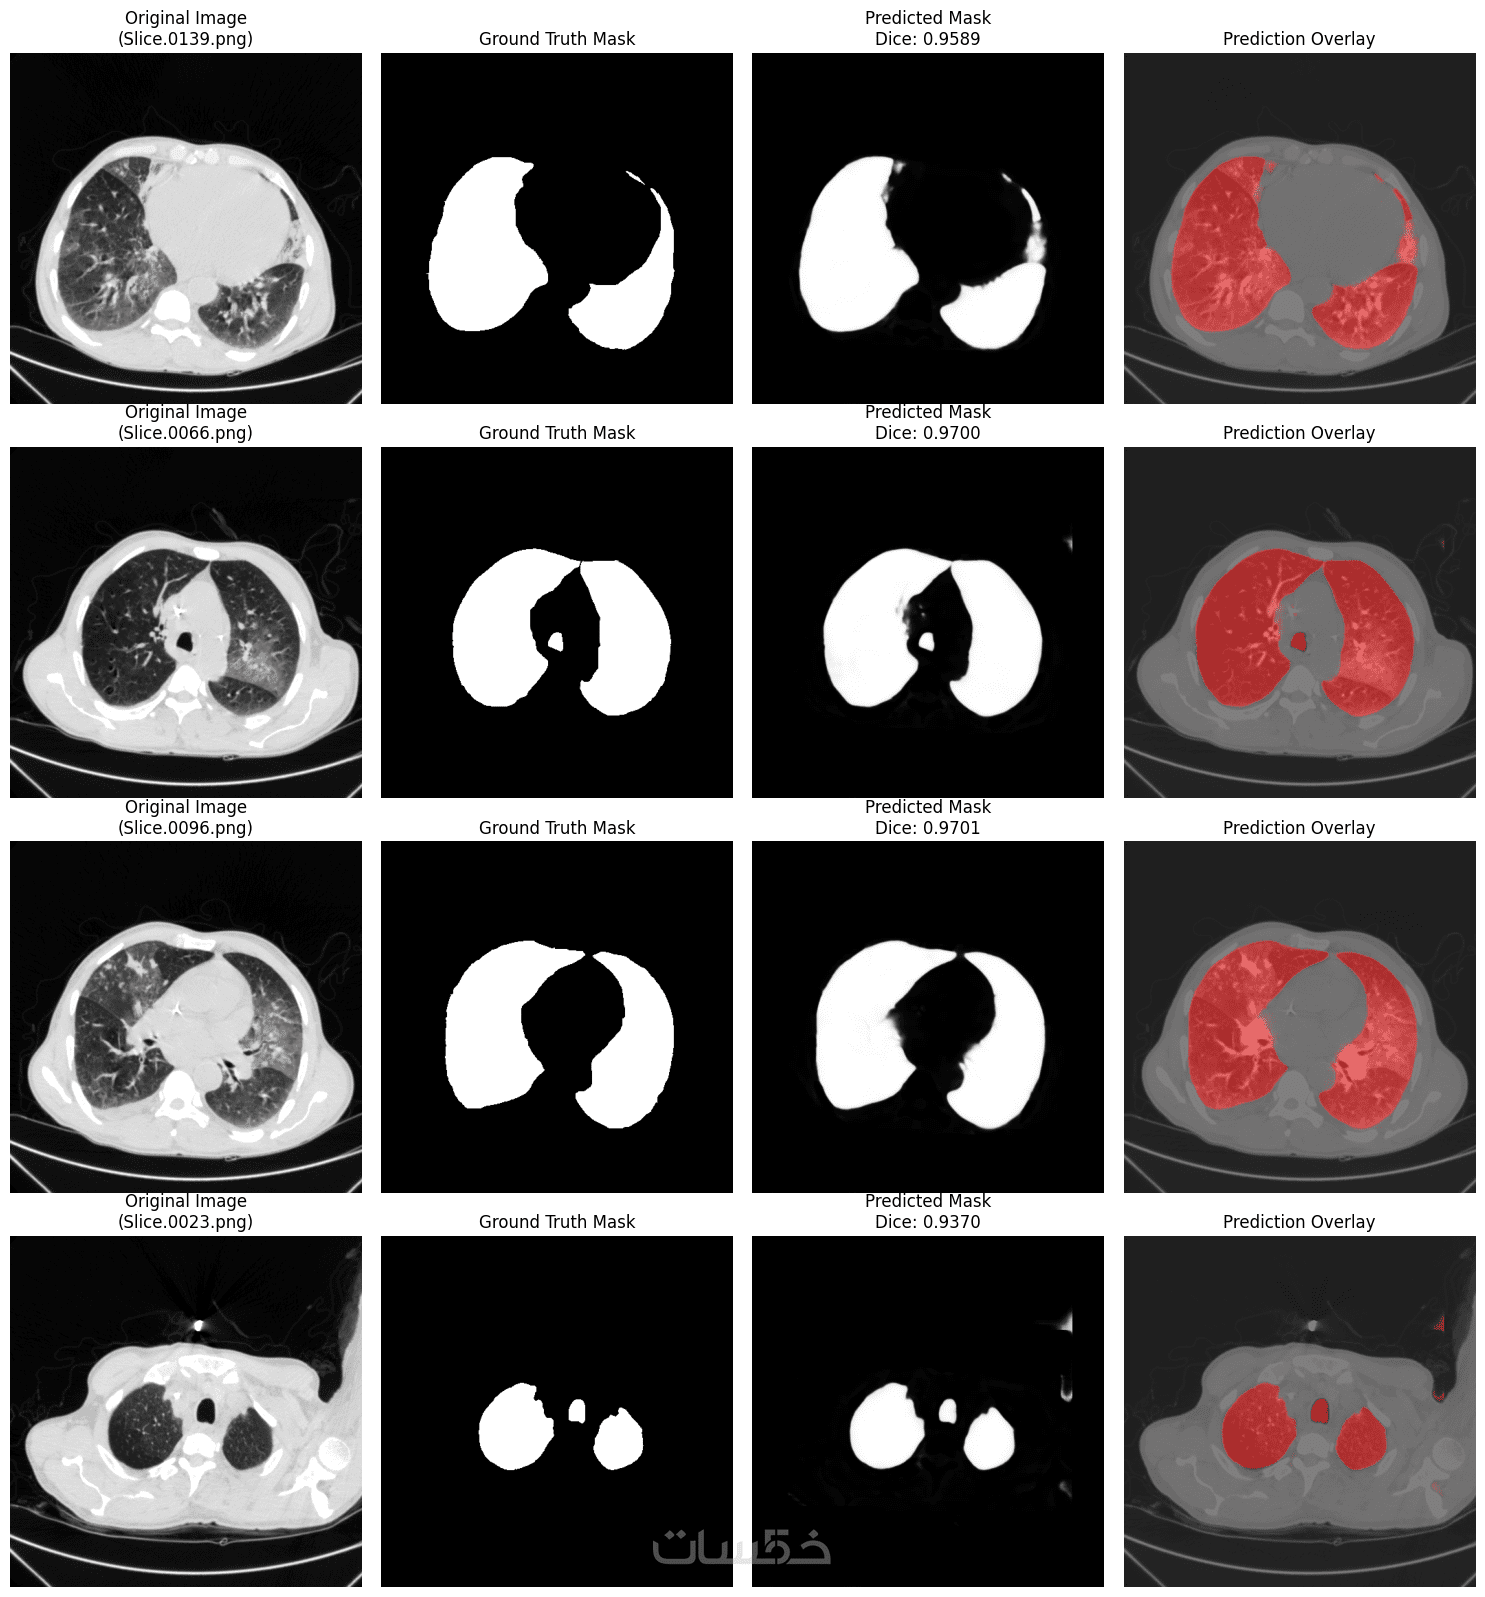

تصميم وتطوير نماذج الرؤية الحاسوبية Computer Vision

ذكاء اصطناعي وتعلم الآلة / الرؤية الحاسوبية

إنشاء نماذج الرؤية الحاسوبية Computer Vision